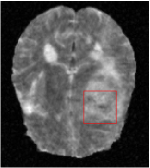

All the experiments are implemented on a Windows workstation with Intel Core i9 CPU at 3.3GHz and an Nvidia GTX-1080Ti GPU with 11GB of graphics card memory via TensorFlow Abadi et al. (2016). The parameters in the proposed network are initialized by using Xavier initialization Glorot and Bengio (2010). We trained the meta-learning network with four tasks synergistically associated with four different CS ratios: 10%, 20%, 30%, and 40%, and test the well-trained model on the testing dataset with the same masks of these four ratios. We have 300 training data for each CS ratio, which amount to total of 1200 images in the training dataset. The results for and MR reconstructions are shown in Tables 5.4 and 5.4 respectively. The associated reconstructed images are displayed in Figures 1 and 3. We also test the well-trained meta-learning model on unseen tasks with radio masks for skewed ratios: 15%, 25%, 35%, and random Cartesian masks with ratios 10%, 20%, 30% and 40%. The task-specific parameter for the unseen tasks are retrained for different masks with different sampling ratios individually with fixed task-invariant parameters . In this experiments, we only need to learn for three skewed CS ratios with radio mask and four regular CS ratios with Cartesian masks. The experimental training proceed on less data and iterations, where we performed on 100 MR images with 50 epochs. For example, for reconstructing MR images with CS ratio 15% radio mask, we fix the parameter and retrain the task-specific parameter on 100 raw data with 50 epochs, then test with renewed on our testing data set with raw measurement that sampled from radio mask with CS ratio 15%. The results associated with radio masks are shown in Table 5.4 and 5.4, Figure 2 and 4 for and images respectively. The results associated with Cartesian masks are list in Table 5.4 and reconstructed images are displayed in Figure 5.

Qualitative comparison between conventional and Meta-learning methods are shown in Figure 1 and 3, which display the reconstructed MR images of the same slice for T1 and T2 respectively, we label the zoomed-in details of HGG in the red boxes. We observe the evidence that conventional learning is more blurry and lost sharp edges, especially in lower CS ratios. From the point-wise error map, we find meta-learning has the ability to reduce noises especially in some detailed and complicated regions comparing to conventional learning.

In this section, we test the generalizability of the proposed model that tests on unseen tasks. We fix the well-trained task-invariant parameter and only train for sampling ratios 15%, 25% and 35% with radio masks and sampling ratios 10%, 20%, 30% and 40% with Cartesian masks. In this experiment, we only used 100 training data for each CS ratio and apply a total of 50 epochs. The averaged evaluation values and standard deviations are listed in Table 5.4 and 5.4 for reconstructed T1 and T2 brain images respectively that proceed with radio masks, and Table 5.4 shows the qualitative performance for reconstructed T2 brain image that applied random Cartesian sampling masks. In T1 image reconstruction results, meta-learning improved 1.6921 dB in PSNR for 15% CS ratio, 1.6608 dB for 25% CS ratio, and 0.5764 dB for 35% comparing to the conventional method, which in the tendency that the level of reconstruction quality for lower CS ratios improved more than higher CS ratios. A similar trend happens in T2 reconstruction results with different sampling masks. The qualitative comparisons are illustrated in Figure 2, 4 and 5 for T1 and T2 images tested in skewed CS ratios in radio masks, and T2 images tested in Cartesian masks with regular CS ratios respectively. In the experiments that conducted with radio masks, meta-learning is superior to conventional learning especially at CS ratio 15%, one can observe that the detailed region in red boxes keeps edges and is more close to the true image, while conventional method reconstructions are hazier and lost details in some complicated tissue. The point-wise error map also indicates that Meta-learning has the ability to suppress noises.